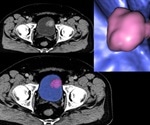

Gastrointestinal Stromal Tumor (GIST) Diagnosis